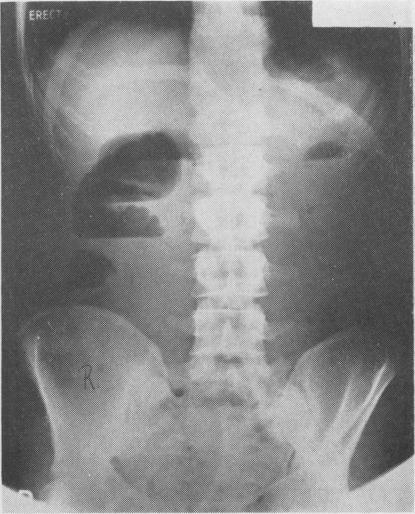

BOOTH C C

Postgrad Med J. 1961 Dec;37(434):725-39. doi: 10.1136/pgmj.37.434.725.